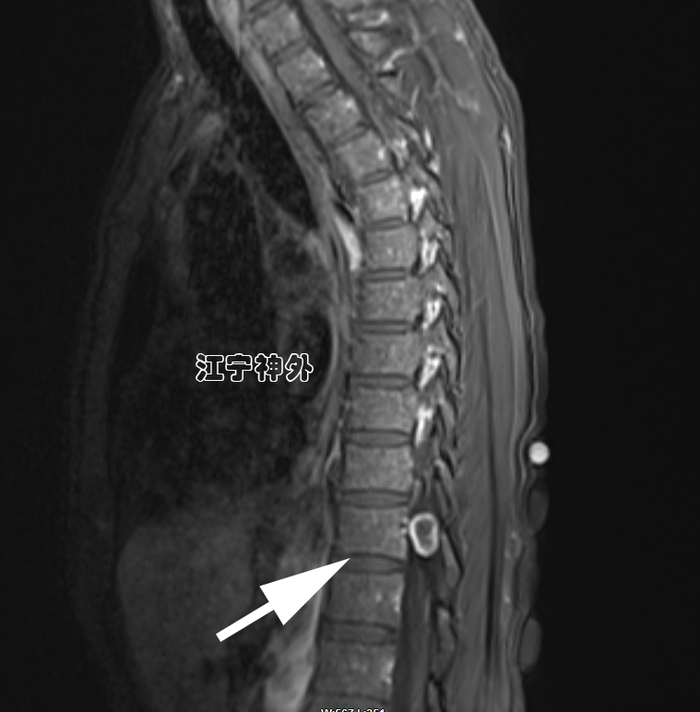

术后磁共振显示,肿瘤无任何残留,脊髓圆锥和神经根恢复正常形态,术后大小便功能、下肢运动恢复正常。术后病理提示:神经鞘瘤伴出血。